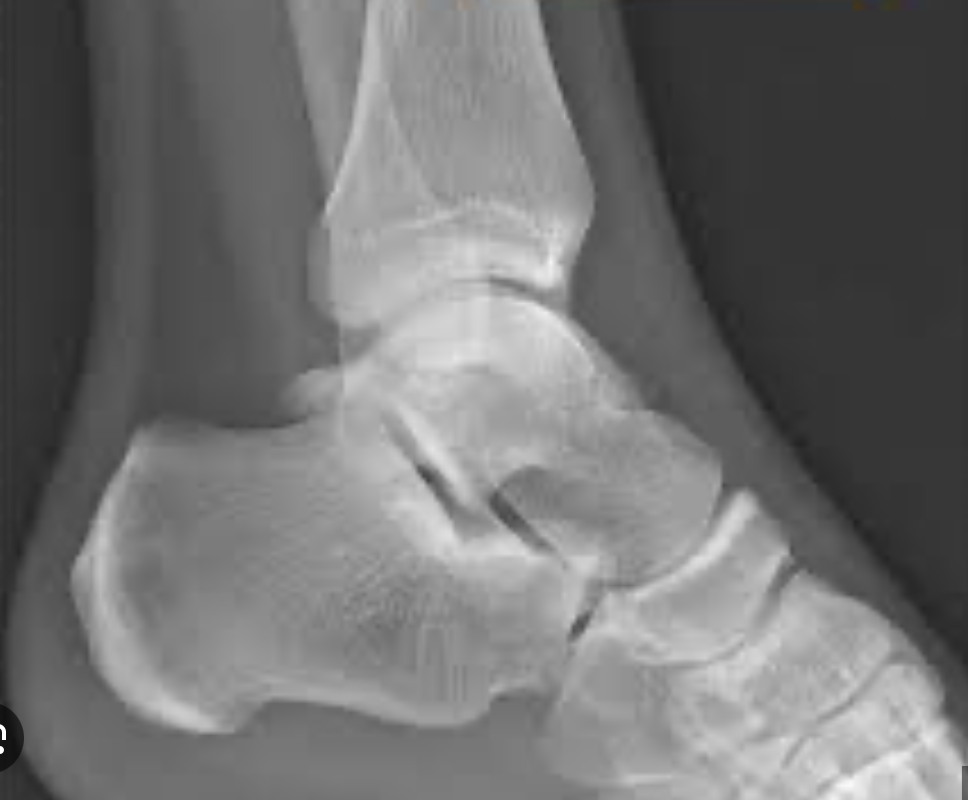

Rx en esguince de tobillo

Edema de tejidos blandos

Aumento del espacio entre perone y astragalo

Como pedir Rx en esguince de tobillo?

Con estrés

Q

Rx esguince